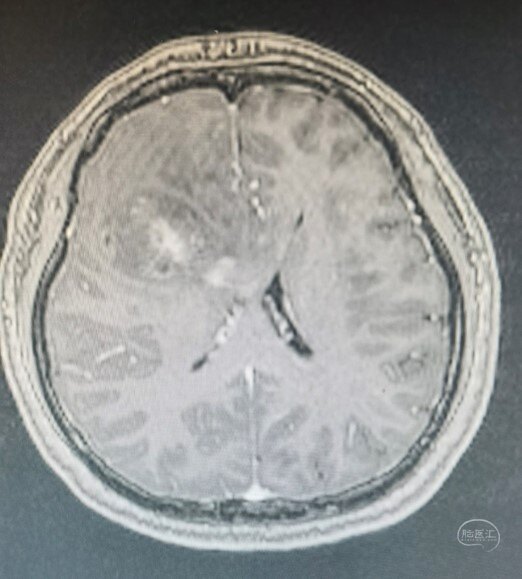

术前增强T1